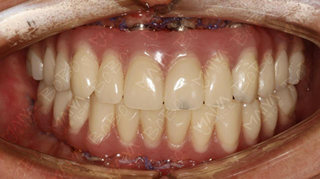

术后照片